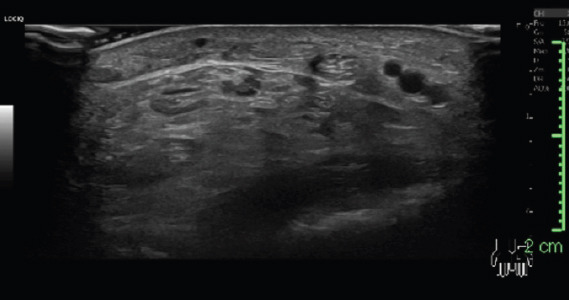

Materials & methods: This retrospective study analyses medical records of patients diagnosed with acute carpal tunnel syndrome from 2021 to 2023 within our coverage area. Information was extracted from medical records, including diagnostic codes and clinical assessments for all cases of acute carpal tunnel syndrome, diagnosed during the period from 2021 to 2023. Data analysed, include age, sex, medical history, symptoms, mechanism of injury, clinical features, imaging, management, and follow-up. Six native Scottish patients, aged 43 to 65, developed acute carpal tunnel syndrome due to various causes, including flexor sheath infection, wrist soft tissue injury, distal radius fractures (with and without plate fixation), and scaphoid fracture.